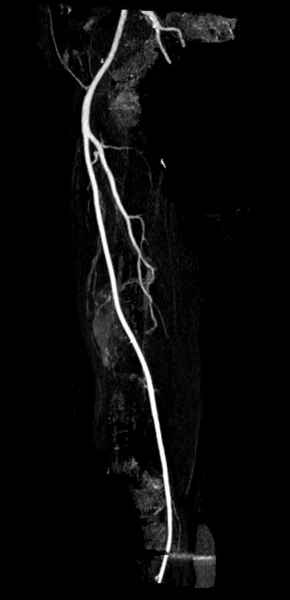

Для предупреждения кровотечения во время рассверливания, за день до операции провели эмболизацию сосудов питающий метастаз. http://radiology.rsnajnls.org/cgi/reprint/150/3/673.pdf (7-11, 12-15-16)

С минимальным рассверливанием и ретроградным методом провели остеосинтез бедра 12 мм гвоздем. (17-20)